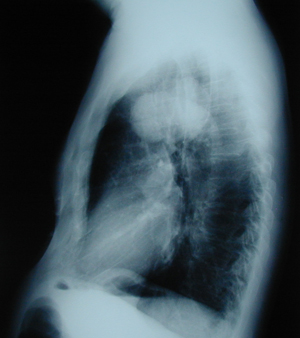

Figure 2

Lateral chest X-ray. A huge mass located in the right upper lobe, at the aortic arch level.